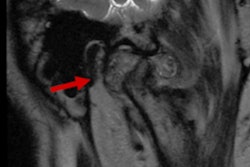

There was an increase in the number of scans in patients between the ages of 6 and 12 between 2017 and 2020. Most often, imaging was ordered to assess dentigerous cysts and impacted teeth. Since it is important to master the use of CBCT in pediatric patients in the right indications, clear, thorough guidelines for the use of CBCT in children are needed, the study's authors wrote.

Many different reasons were provided as to why the children needed to undergo CBCT scans. Assessment of impacted teeth (about 46%) was the most frequent reason for referral, while the least frequent reason was the evaluation of bone pathosis (about 10%), the authors wrote.